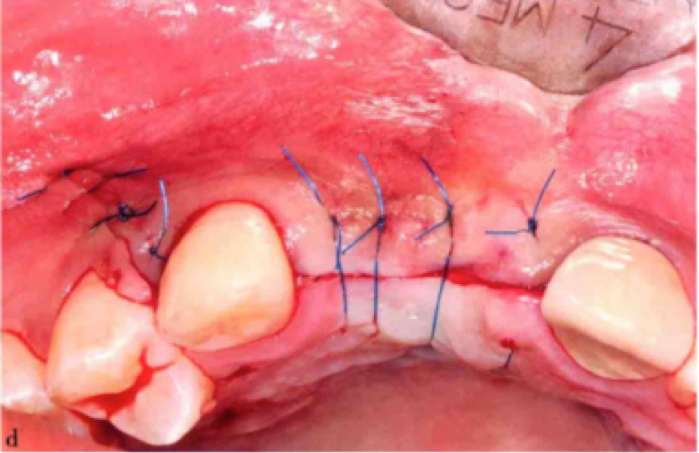

STEP 5:缝合

必须实现无张力的初期创口关闭,通常,骨移植之后黏膜量不足,可在粘骨膜瓣基底部行骨膜切开,松弛粘骨膜瓣,使粘骨膜冠向推进,关闭创口。通常用4-0缝合线行褥式或单线间断缝合关闭创口。

(术后缝合。图源自林野版口腔种植学教材)